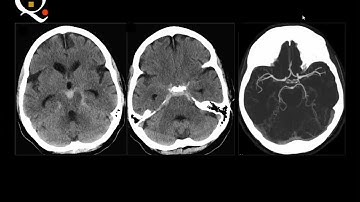

Brain imaging quiz cases (5) - Prof Mamdouh Mahfouz